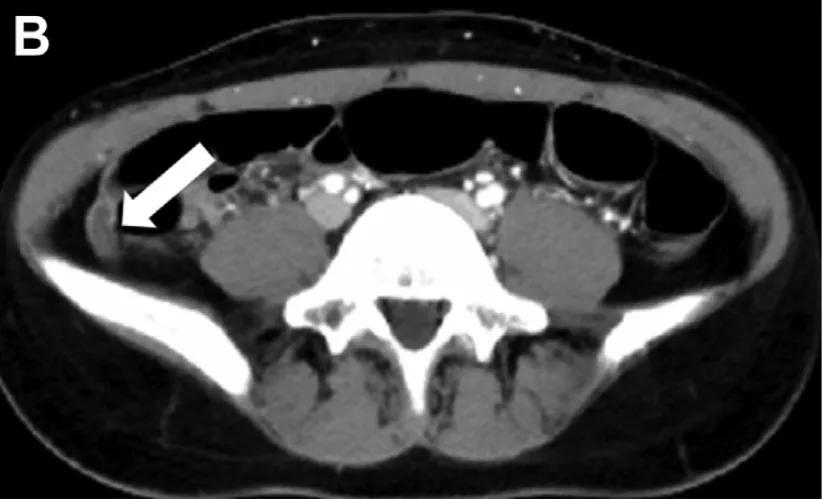

在阑尾切除术中,医生发现阑尾腔内存在大量血块。

并见一血管样结构突出于阑尾粘膜,宽度大约3mm左右(头和尾的宽度大约一致,无变窄或变宽)(图D)。